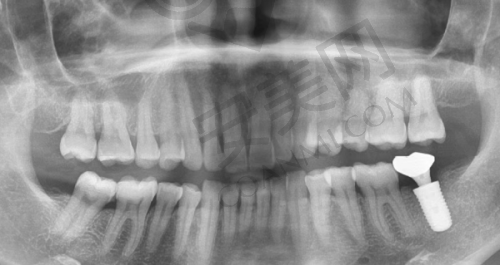

创英种植牙的手术过程一般分为几个步骤。首先,患者需要到柳州中瑞口腔进行全方面的口腔检查,包括口腔CT扫描等,以确定患者的口腔状况和牙槽骨条件。刘轩医生会根据检查结果制定详细的种植方案。然后,在局部麻醉下,医生会在患者的牙槽骨上制备一个合适的种植窝,将种植体植入其中。植入后,需要等待一段时间,让种植体与牙槽骨充分结合,这个过程通常需要几个月的时间。之后,医生会安装基台和牙冠,完成整个种植牙的修复过程。在整个手术过程中,刘轩医生会严格遵循无菌操作原则,确保手术的安心和成功。